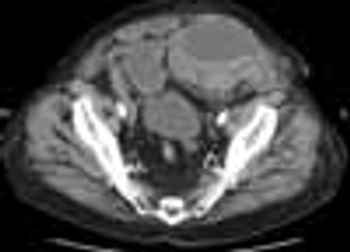

A30-year-old man complains of chest pain, dyspnea, fever, and nonproductivecough that began earlier in the day. The pain is constant and does notdiminish with rest; it worsens somewhat with deep inspiration and has localizedto the left chest. The patient has had no nausea, vomiting, or abdominal pain.He has been immobile for several years secondary to spinal cord disease buthas no history of cardiopulmonary disease.